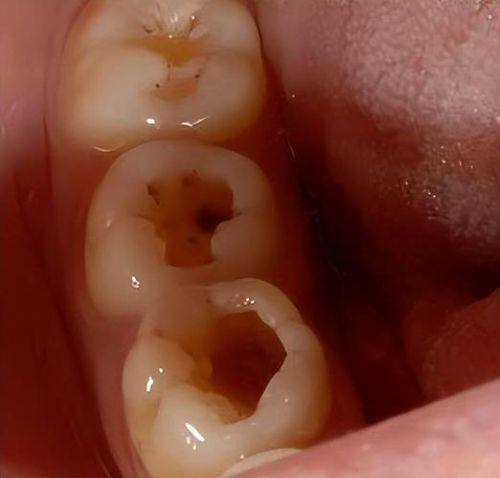

你是否正担忧龋齿不断腐蚀牙齿,却又不想立刻去治疗?别着急!本文为你带来5个实用技巧,帮助你在不治疗的情况下,让龋齿停止腐蚀。这些技巧涵盖日常口腔护理、饮食调整等方面,简单又有效。掌握这些方法,能让你更好地保护牙齿,提升口腔健康水平。接下来,就一起看看这些实用技巧吧!

当发现牙齿出现黑斑或有敏感症状时,一定要尽早就诊。特别多人觉得牙齿有点小问题不用管,殊不知,这可能会让龋坏越来越重度。如果龋坏进展至牙髓,那就会引发剧烈疼痛,到时候治疗起来不仅更麻烦,自己也要受更多的苦。所以,一旦发现牙齿有异常,就别犹豫,尽快去看医生,这样能避免问题恶化,让牙齿保持健康。